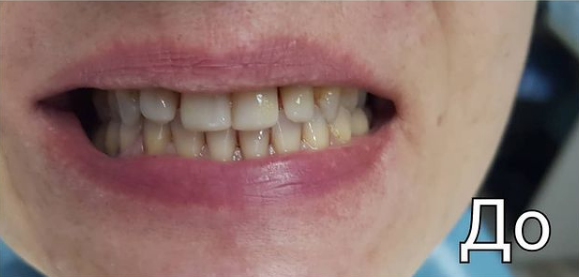

Стоматологическая клиника МИЛА ДЕНТ (MILA DENT)

Протезирование зубов